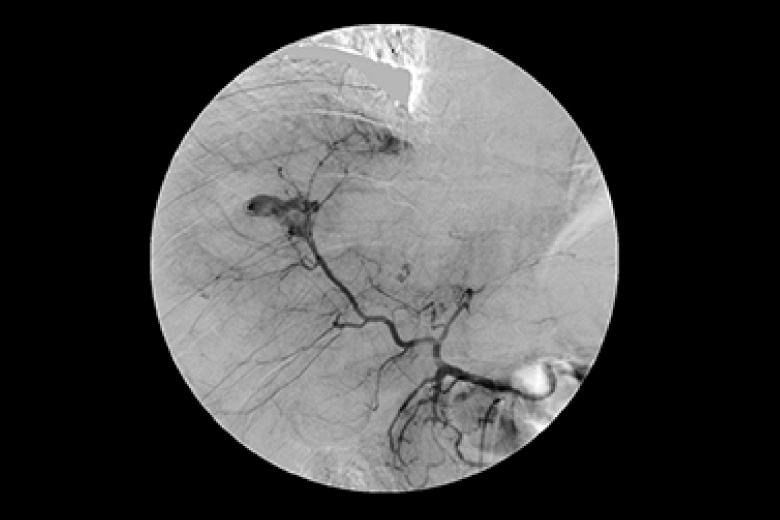

血管の中に造影剤を注入して脳、心臓、肝・胆道・膵、腎、四肢などの血管を造影診断、治療します。 心臓を中心とし検査を行う装置と腹部を中心とした検査をおこなう装置(IVR-CT)にて検査、治療をおこなっております。 心臓検査ではバイプレーン(2管球)装置のため少ない造影剤で検査を受けることができます。また腹部装置は80列CTとの組み合わせのためより高精細な画像が収集でき3Dガイド下にて検査・治療を行っています。

肝臓損傷(出血)